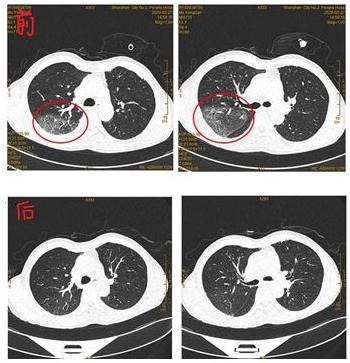

田某某,多次我院血液科和消化科住院,诊断骨髓增生异常综合征及肝硬化等多种疾病。消化科住院期间,突然发热,2月27日复查肺CT显示双肺新发广泛肺泡内渗出(磨玻璃密度灶),感染性病变可能性大,不排除是病毒性肺炎。患者本身就是易感人群,如果是新冠肺炎,可能会造成消化科的值班医护人员和在院内其他患者感染。为消除隐患,决定将田某某转到隔离病房,边进行原发病治疗,边筛查病毒核酸排查。期间血小板降低至14x10*9/L,隔离病房给予紧急输血小板治疗。两次病毒核酸检测结果为阴性,排除感染新冠肺炎,抗感染、利尿等综合治理后,患者未再发热,全身浮肿有消退,一般生命征尚稳定,3月1日复查肺CT提示双肺多发炎症,较前吸收减少,予以转回消化科继续专科治疗。整个过程顺利,患者及家属都表示满意。